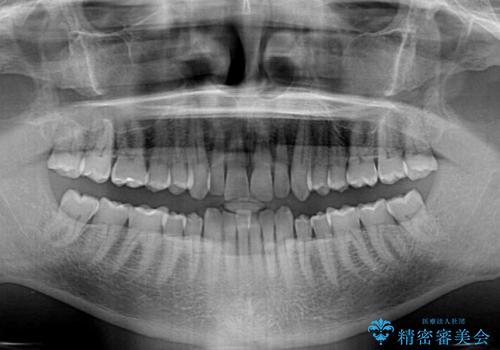

- 前歯のデコボコを気にして来院された患者様です。

インビザラインでもワイヤー装置でも対応可能でしたが、仕事の都合で来院回数を減らしたいとのことでインビザラインによる矯正治療を選択されました。

著しく咬合力が強いため、奥歯がしっかりと噛めずに治療が長引くことが懸念されました。

1セット目のインビザラインを使用した際には左右ともに大臼歯が咬み合っていなかったのですが、2セット目できっちりと仕上げることができました。